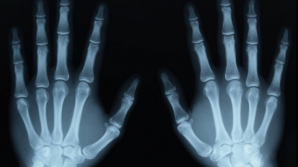

SEMNAL DE ALARMĂ: Tinerii dezvoltă oase asemănătoare unor coarne, din cauza utilizării telefonului mobil